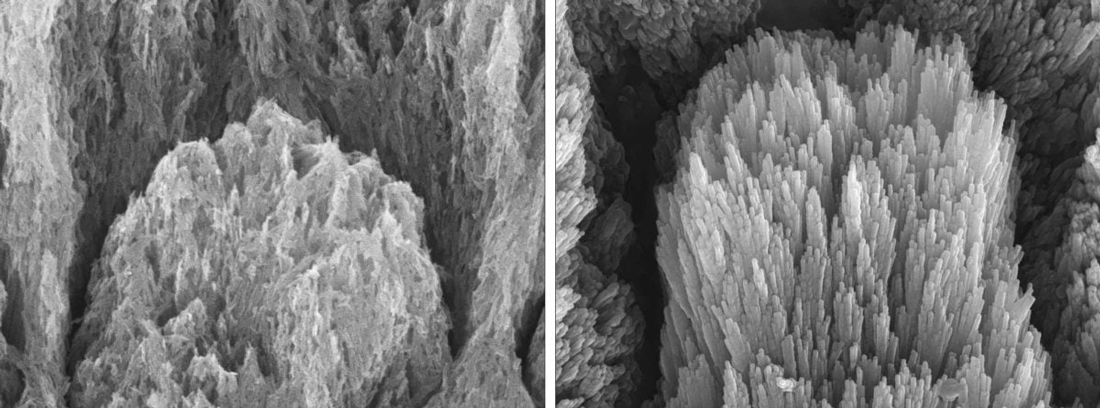

تصاویر میکروسکوپ الکترونی از دندانی با مینای دندان از بین رفته، که کریستالهای آپاتیت فرسوده را نشان میدهد (سمت چپ)، و یک دندان مشابه پس از دو هفته درمان که کریستالهای مینای دندان بازسازیشده بهصورت اپیتاکسیال را نشان میدهد (سمت راست).

او ادامه میدهد: «زمانی که ماده ما روی مینای دندان از بین رفته یا فرسوده، یا عاج نمایان اعمال میشود، رشد کریستالها بهصورت یکپارچه و سازمانیافته تشویق میشود و ساختار طبیعی و سالم مینای دندان بازیابی میگردد. ما خواص مکانیکی این بافتهای بازسازی شده را در شرایط شبیهسازیشده “زندگی واقعی”، مانند مسواک زدن، جویدن و تماس با غذاهای اسیدی، آزمایش کردیم و مشاهده شد که مینای بازسازیشده دقیقاً مانند مینای سالم رفتار میکند.»